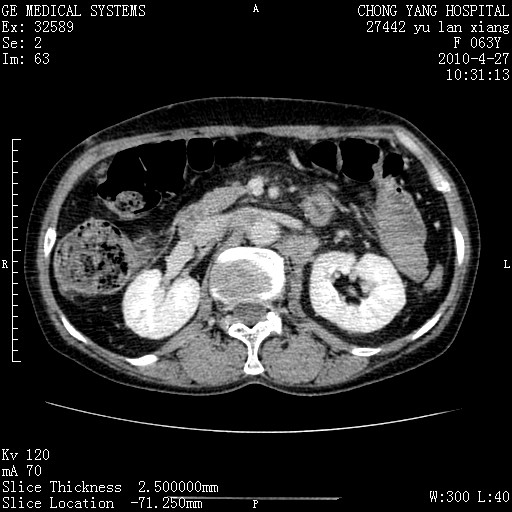

标题: CT26066:F63Y 上腹正中压痛半月,CA199:7400u/ml,MR示胰腺炎伴 [打印本页]

胰腺癌侵犯腹腔动脉干-分支、胃壁、左侧膈肌伴胰周及腹膜后淋巴结转移、胆囊切除术后。

胰腺癌侵犯腹腔动脉干-分支、胃壁、左侧膈肌伴胰周及腹膜后淋巴结转移、胆囊未显影。